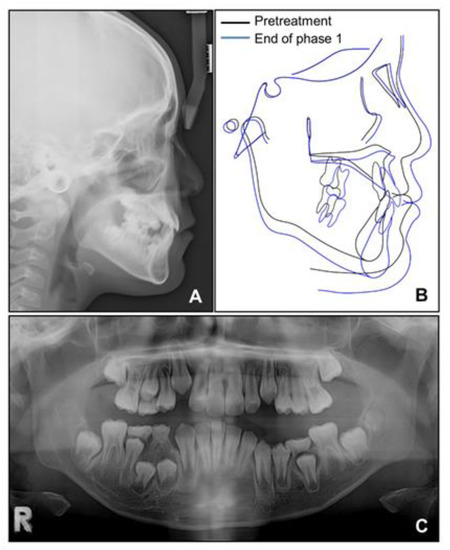

Based on this, we decided to start an orthopedic treatment and closely follow up the hypertrophic region. We placed a bonded rapid palatal expansion appliance with a hook for the face mask, and the screw was turned once a day for 2 weeks. The separation of the midpalatal suture was confirmed, and the face mask was set up with the instruction of wearing it for at least 14 h a day. After 5 months, the crossbite was relieved, and the anteroposterior jaw relationship was improved. Nevertheless, there was still a lack of space for the eruption of permanent teeth on the maxillary dentition (Figure 4A). We stopped the use of the face mask and set up an active removable appliance on the maxilla to gain space. After 18 months, sufficient space was made on the maxillary dentition, and we decided to finish the phase 1 treatment (Figure 4B and Figure 5).

Figure 5. Radiographs after phase 1 treatment. (A) Lateral cephalogram; (B) Superimposition before and after phase 1 treatment; (C) Panoramic radiograph.